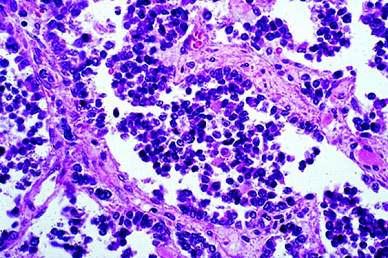

What type of rhabdomyosarcoma is shown in the given image? _____